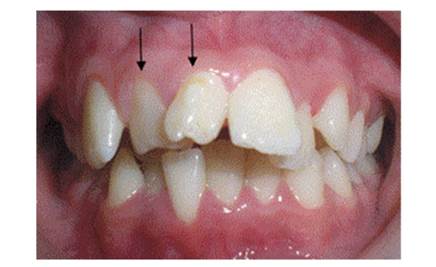

Figure 1 and Figure 2 show the front and occlusal images of an 11-year-old male patient who consulted the Universidad del Valle Clínica de Odontología Integral del Niño y del Adolescente. The patient does not have a history of relevant medical conditions or systemic conditions, nor background of dental anomalies of number in his family.

Figure 1 Front view. The arrows point to the supernumerary teeth; note that these are two supplemental dysmorphic teeth

The patient had two mesiodens that have signifi cantly displaced the central incisors and lateral incisors. The mesiodens have the shape of incisors with multiple tubercles.

It is not common to find erupted upper permanent incisors in relation to molariform, supplemental, or tuberculate mesiodens, contrary to what happens with conical-shaped mesiodens.10)(32)(34) As opposed to what was reported in the literature in case 1 reported here, the presence of two mesiodens did not block eruption of the lateral right central incisor, although it resulted in displacement of the upper right central incisor to the zone corresponding to the right upper canine, as well as marked palatalization of the upper right lateral incisor, affecting the patient′s occlusal harmony, appearance, and functionality.